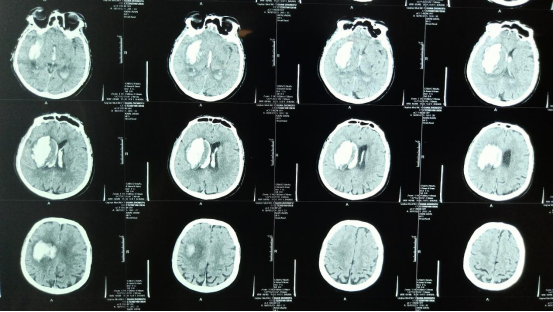

患者管某,男性,58岁,于6月12日晨被发现匍匐于地,意识不清,身边可见大量呕吐物,因患者独自一人生活,具体发病时间不详,家人将其急送至我院。入院时患者浅昏迷,双眼球固定,瞳孔等大,直径2.5mm,有光反应,左侧病理征阳性,GCS6分。经凝血机制和CTA检查排除其它出血性疾病,头部CT显示右侧基底节出血破入脑室,中线结构尚可,术前无创颅内压检测提示颅内压25mmHG,从术前影像判断患者发病时间较长,出血稳定,故决定尽早行微创手术治疗,试图有利于降低增高的颅内压,尽快恢复病人神志和瘫痪肢体活动。

术前影像